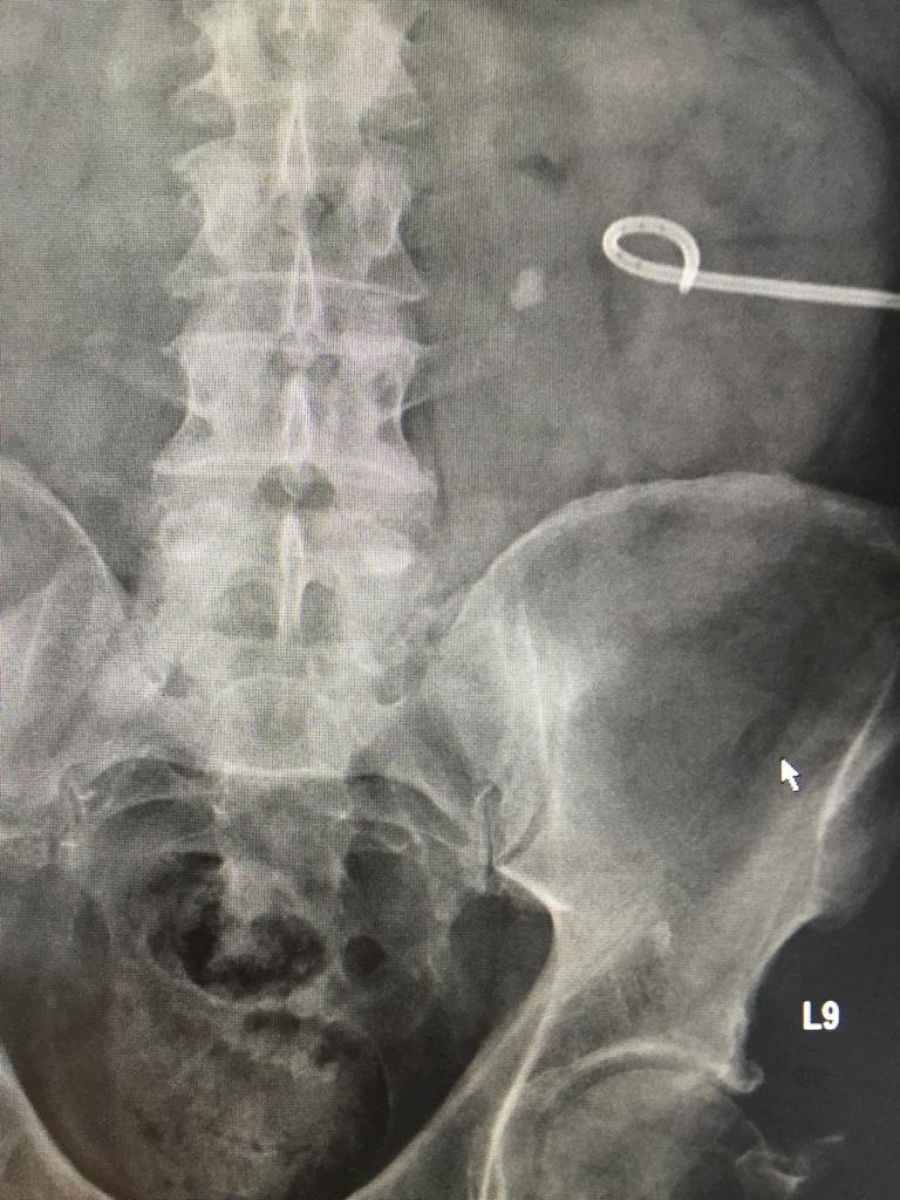

W ostatnich dniach w Samodzielnym Publicznym Zespole Opieki Zdrowotnej w Kędzierzynie-Koźlu zespół urologów przeprowadził nowatorski zabieg leczenia złożonej kamicy moczowej metodą ECIRS. Metoda ta polegającej na jednoczasowym usunięciu złogu nerkowego zajmującego całą nerkę (tzw. kamica odlewowa). Zabieg taki przeprowadzono po raz pierwszy w woj. opolskim.

Leczenie operacyjne polega tutaj na jednoczasowym, endoskopowym (małoinwazyjnym) dostępie do układu kielichowo-miedniczkowego nerki i precyzyjnym usunięciu złogu. Metoda ta jest przyszłością leczenia kamicy moczowej. Z uwagi na małą inwazyjność i precyzję ogranicza ona znacznie pole operacyjne i pomaga zdecydowanie szybciej wrócić pacjentowi do pełnej sprawności. Zabieg ten jest obecnie wykonywany jedynie w zaawansowanych jednostkach medycznych i wymaga specjalistycznego sprzętu oraz wykwalifikowanego, wielozadaniowego zespołu.

Jak powiedział Kierownik Oddziału Urologii i Onkologii Urologicznej lek. med. Michał Pułtorak – Operowany przez nas Pacjent miał złożony typ kamicy moczowodowej i kamicę kielicha dolnego nerki lewej. Stąd decyzja o wykonaniu tego typu zabiegu. Zabieg przeprowadziliśmy korzystając ze wszystkich dostępnych nowoczesnych urządzeń m.in lasera, maloinwazyjnego zestawu do pcnl i ureterorenoskopu półsztywnego. Dzięki współpracy specjalistów udało się usunąć złogi całkowicie.